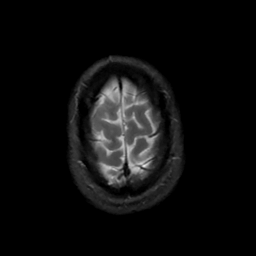

MR Study #3, February 24, 1991 -- Slice #45

[Home][Help][Clinical][Tour 1][Tour 2] Slice 45